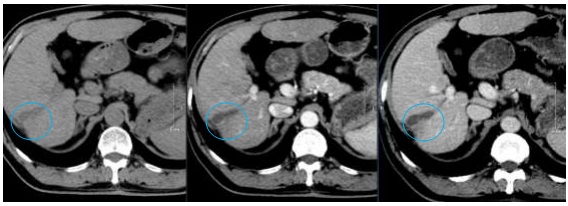

Hình 5: Hình ảnh CT ổ bụng trước điều trị (11/2019): U gan hạ phân thuỳ VI, kích thước 2,5×3,5cm, ngấm thuốc tính chất HCC (vòng tròn đỏ)

Nhận xét: Trước điều trị khối u ngấm thuốc điển hình của HCC (hình 5), tuy nhiên sau điều trị ở thời điểm 9 tháng trở đi khối u giảm về kích thước, không ngấm thuốc sau tiêm nên đạt được bệnh đáp ứng hoàn toàn theo tiêu chuẩn mRECIST (hình 6,7,8,9).